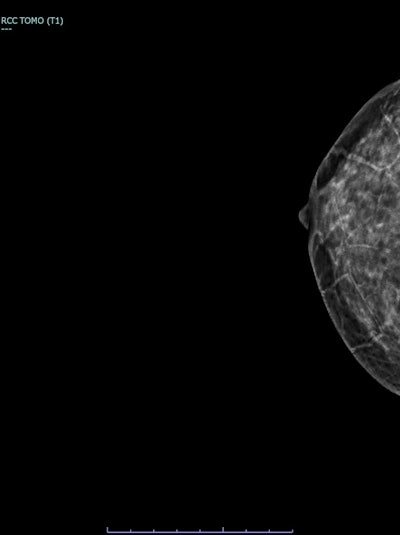

Synthesized 2D mammogram, right breast, craniocaudal (CC) projection of the same patient. No mammographic abnormality is seen. Sensitivity is markedly reduced by dense breast tissue. A retroglandular silicone breast implant is present.